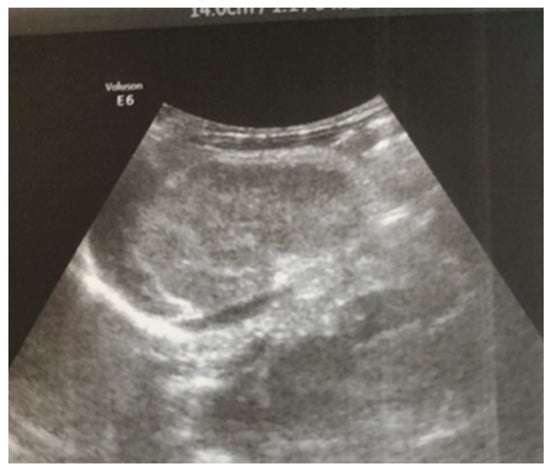

Complex therapy was performed—mechanical ventilation, antibiotics in doses adjusted according to creatinine clearance, anticonvulsants, low-molecular-weight herapin (Enoxaparin), inotropic (Dopamine), and phototherapy. The child’s condition gradually improved and he was extubated on the 9th day of the stay in the NICU. An uncomplicated post-extubation period followed. In the following 2–3 days, macroscopic hematuria was observed. On the second day after extubation, the child’s diuresis was good. The condition of the right kidney was monitored by ultrasound on the 3rd day (Figure 3), the 10th day (recovery of renal venous blood flow was observed), and at the end of the first month. On the 10th day, a decrease in kidney size was noted, and at the end of the first month, the size was below the norm for the age—i.e., the onset of renal atrophy. Follow-up examinations at 6 months and 1 year showed evidence of the atrophying of the right kidney with a longitudinal size of 2 cm, the occurrence of compensatory hypertrophy of the left kidney, normal blood pressure, and preserved renal function (Figure 4).

Although renal blood flow was restored by the 10th day, progressive atrophy of the affected kidney gradually occurred in the case presented (Figure 4). According to a study by Winyard et al. involving 23 children with neonatal thrombosis over a 15-year period [12], the length of the affected kidney exceeding 6 cm (as in our case) is typically associated with the development of renal atrophy, regardless of the treatment administered.

Figure 4. Right kidney image at 1 year of age—reduced in size, with a longitudinal size of 2.6 cm, increased echogenicity of the parenchyma, and the presence of a small subcortical cyst.